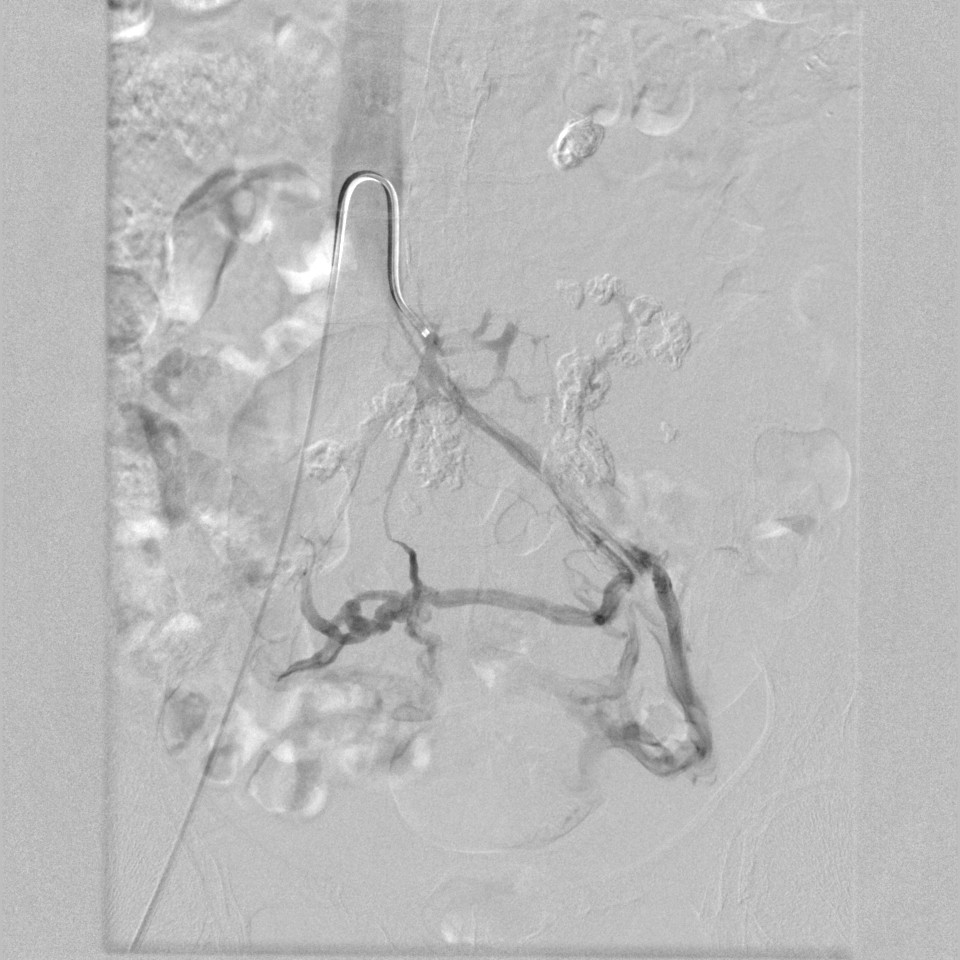

門靜脈高壓治療

tips手術(shù)治療前

tips手術(shù)治療后

有效降低門靜脈壓力,降低消化道出血及腹水等相關(guān)并發(fā)癥,本技術(shù)省內(nèi)領(lǐng)先。